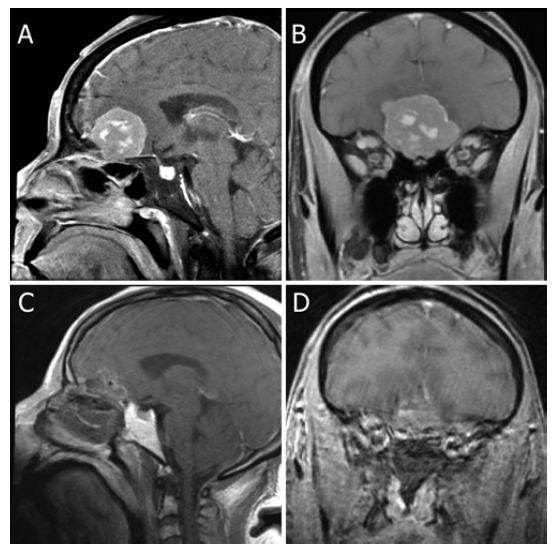

图3. A-B.术前MRI显示OGM;C-D.内镜下经鼻入路切除OGM术后的MRI成像。